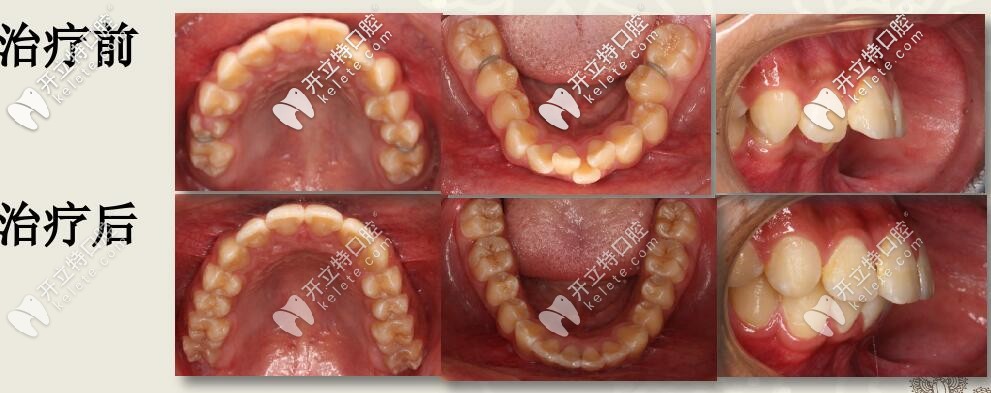

深復(fù)蓋凸嘴伴下巴后縮,直絲弓聯(lián)合擴(kuò)弓,斜導(dǎo)矯正27個(gè)月對(duì)比

12歲兒童齙牙,下巴后縮,牙列擁擠,全口直絲弓配合斜導(dǎo)、擴(kuò)弓器以及激動(dòng)器矯治,27個(gè)月后效果驚人。

今天西安圣貝牙科分享一例12歲兒童齙牙矯正案例,深覆蓋伴隨深覆合,采用雙期聯(lián)合配合肌激動(dòng)器矯治,矯治醫(yī)生是圣貝口腔何曉天醫(yī)生。

肉眼可見上前牙唇傾,輕度擁擠 下頜牙弓寬度窄,前牙區(qū)擁擠,后牙去舌傾明顯,前牙深覆蓋,深覆合

結(jié)束后,牙列整齊,深復(fù)蓋明顯改善。